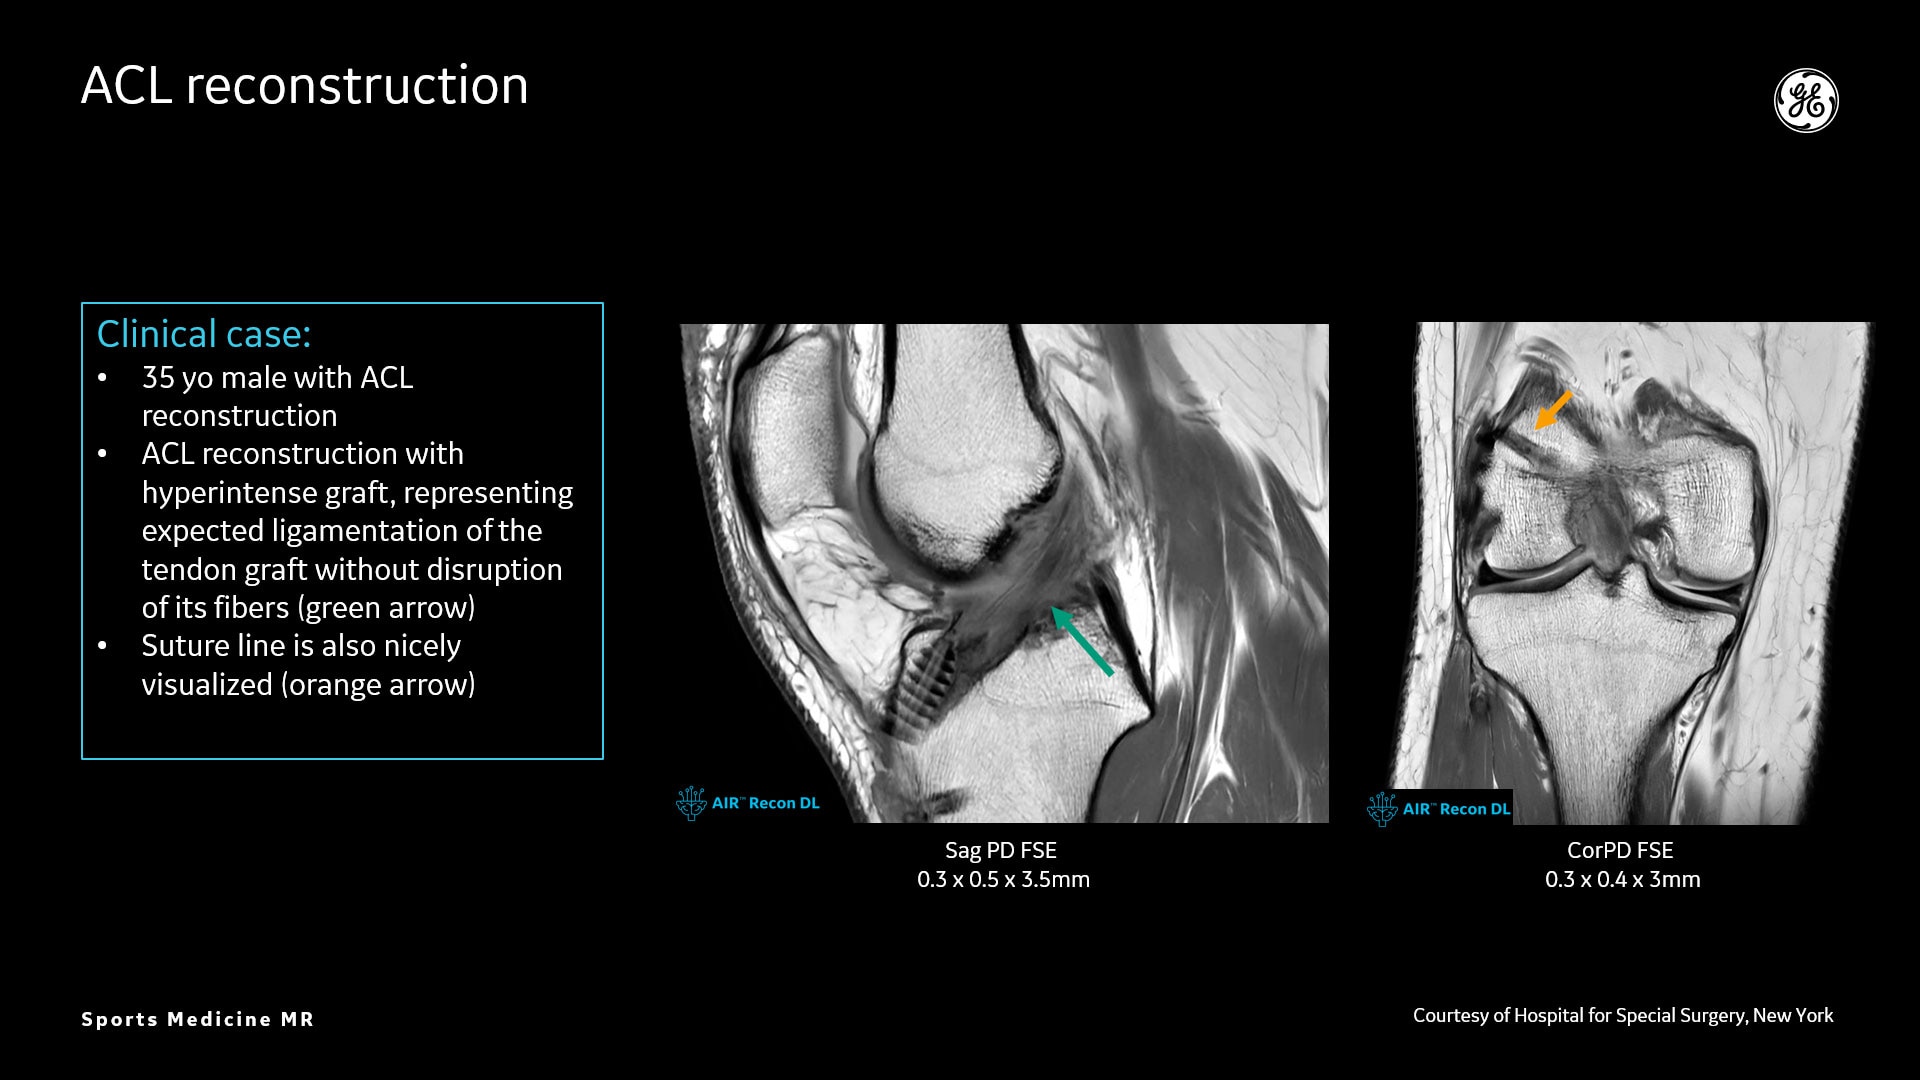

AIR™ Recon DL liefert hochauflösende Bilder mit erhöhtem SNR bei deutlich reduzierten Scanzeiten. Diese Technologie optimiert die Darstellung selbst kleiner Verletzungen wie Meniskus-, Labrum- und Bänderrisse. Die Verkürzung der Scanzeiten erhöht die Flexibilität für individuell abgestimmte MR-Protokolle mit einer zusätzlichen oZTEo-Sequenz für eine detaillierte Frakturbeurteilung.